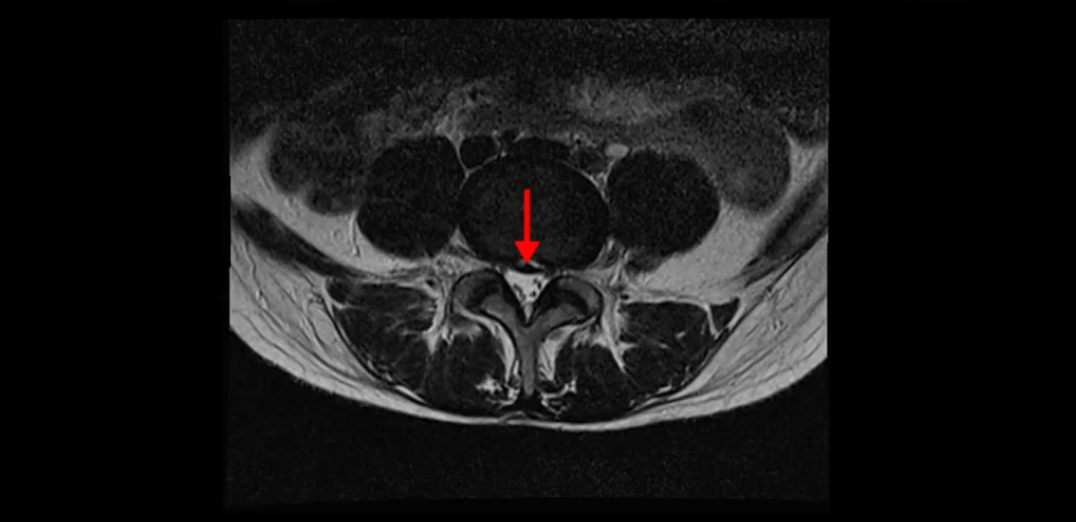

이분 MRI를 보시면 두 마디의 퇴행성디스크가 있습니다. 그리고 디스크가 조금씩 밀려 나와 있고요. 그런데 디스크 탈출 정도는 두 마디 다 심하지 않습니다. 4번 5번에는 디스크 탈출이 약간 있고,

척추관협착도 약간 진행이 되고 있고요.

5번 1번은 디스크 탈출이 가운데 쪽으로 살짝 있습니다.

또한 양쪽 신경 가지가 빠져나가는 추간공은 매우 넓은 상태입니다.

중요한 것은 이 정도 경미한 탈출과 협착으로는 양쪽 다리가 저리고 아플 수가 없습니다.

이분 MRI를 보시면 퇴행성디스크가 있고 약간의 협착이 있지만 이 정도의 퇴행성디스크와 협착으로는 신경이 눌려서 양쪽 다리가 저리고 아픈 증상이 나올 수가 없습니다. 그래서 MRI와 이 환자분의 다리 증상이 매치가 안 된다고 하는 의사들이 많은 겁니다.